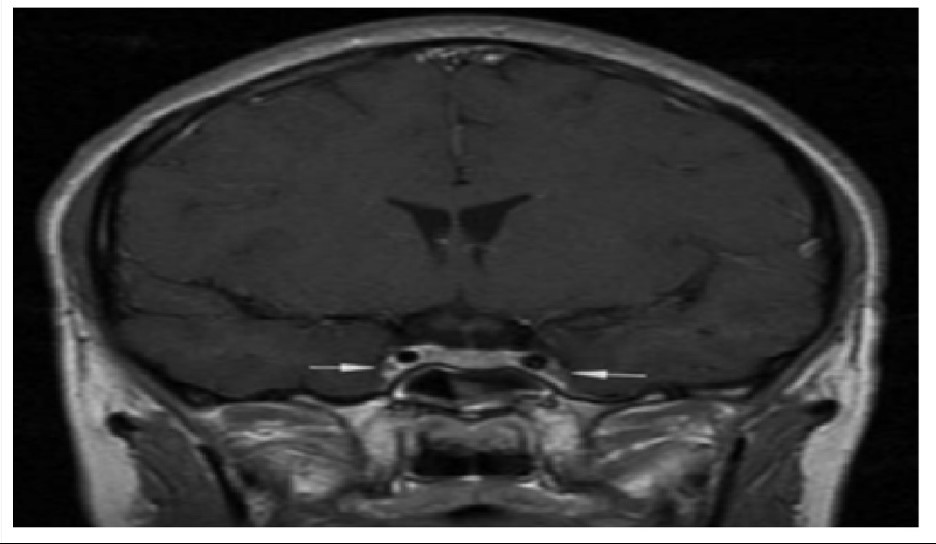

Theo hồ sơ bệnh án, bệnh nhân khởi phát bằng viêm xoang cấp mủ, sau đó chuyển sang viêm tấy nửa mặt, rồi nhanh chóng xuất hiện rối loạn ý thức và co giật. Kết quả chụp cộng hưởng từ sọ não cho thấy: Phù nề lan tỏa, dấu hiệu điển hình của viêm tắc tĩnh mạch xoang hang - một tình trạng huyết khối nhiễm trùng ở nền sọ.

Vị trí mũi tên là viêm và co thắt động mạch cảnh trong 2 bên - Ảnh BVCC